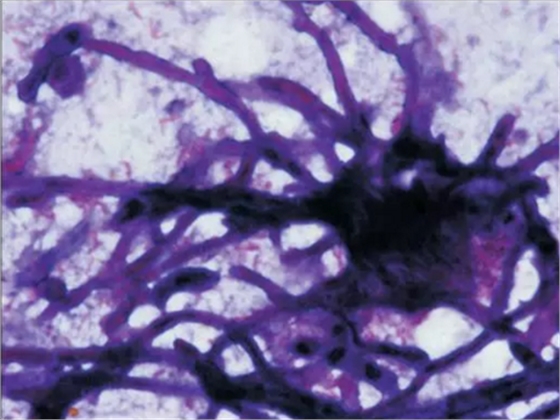

初步診斷為口腔毛霉菌病。取部分軟腭組織做病理學(xué)檢查。病理檢查顯示組織中含有大量無包膜的真菌、壞死血管組織,結(jié)果支持毛霉菌病的診斷。